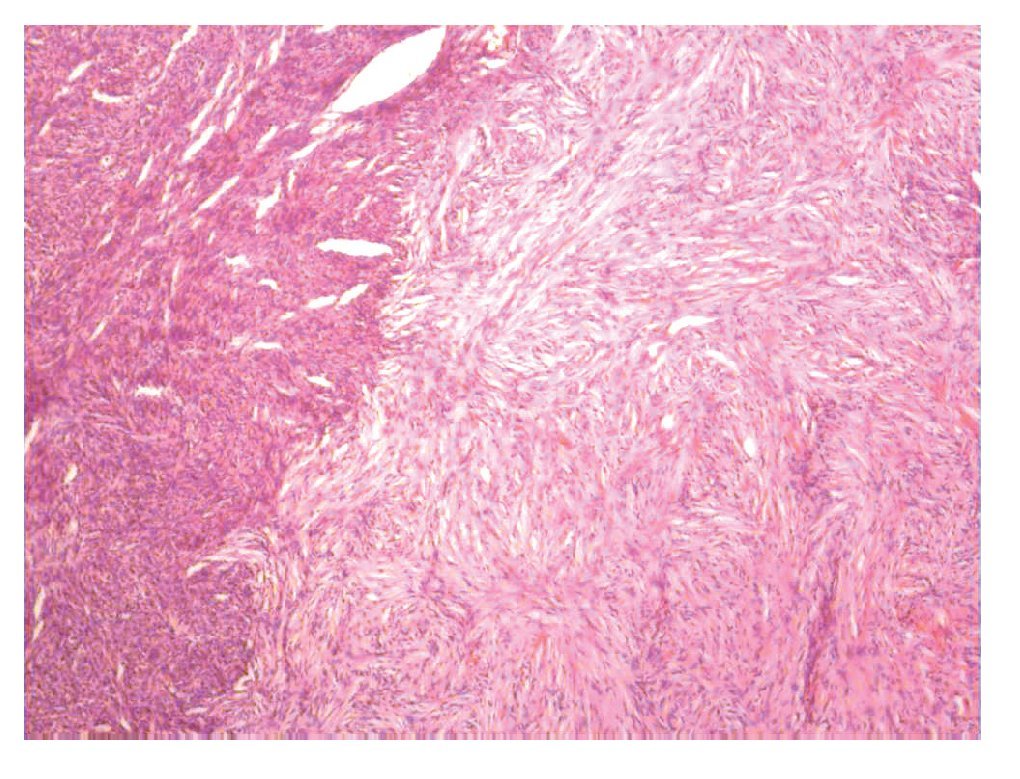

Aspecto microscópico. La mayoría de los casos (62%) estaba compuesto por células fusiformes, dispuestas en un patrón en "rueda de carreta" (Figura 1), con o sin un centro colagenoso acelular central. El número de mitosis promedio en 10 campos a seco fuerte fue de uno a cuatro.

Figura 1. Dermatofibrosarcoma Protuberans variedad convencional, neoplasia fusocelular con patrón en haces cortos que se entrecruzan formando rehiletes (Hematoxilina & eosina).